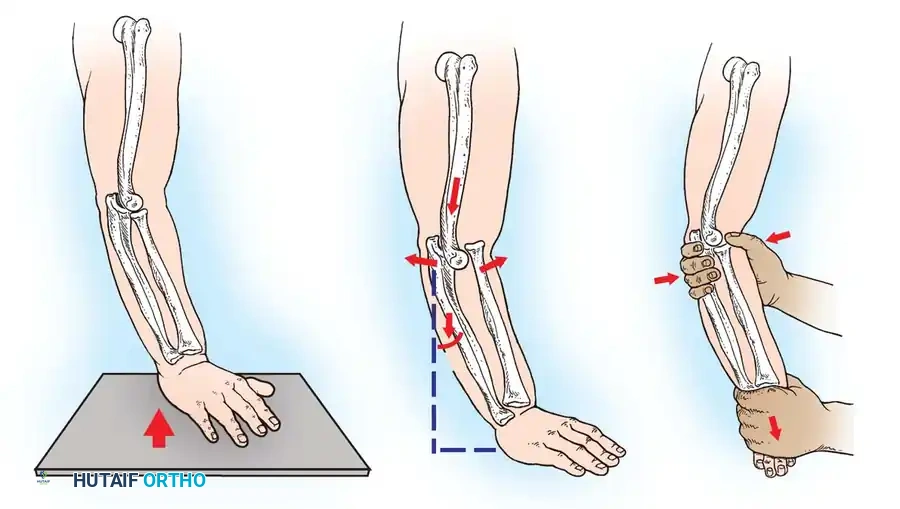

Fig. 33-42 Reduction technique for radial neck fractures.

- Positioning: The patient is placed supine. An assistant firmly stabilizes the distal humerus and the radius distal to the fracture site.

- Maneuver: With the elbow in full extension, the surgeon applies a strong varus stress to the elbow with one hand. This opens the radiocapitellar joint laterally.

- Reduction: Using the thumb of the opposite hand, direct lateral-to-medial pressure is applied over the tilted radial head to lever it back into anatomical alignment.

- Immobilization: The forearm is then placed in 90 degrees of flexion and pronation to lock the reduction.

Fig. 33-45 Mechanism of reduction of radial neck fracture.